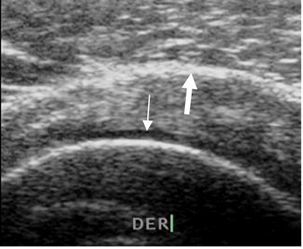

Fig 10. Tendón del supraespinoso normal.

Ecografía vista coronal. Cartílago articular (Flecha delgada) y bursa SASD. (Flecha gruesa).